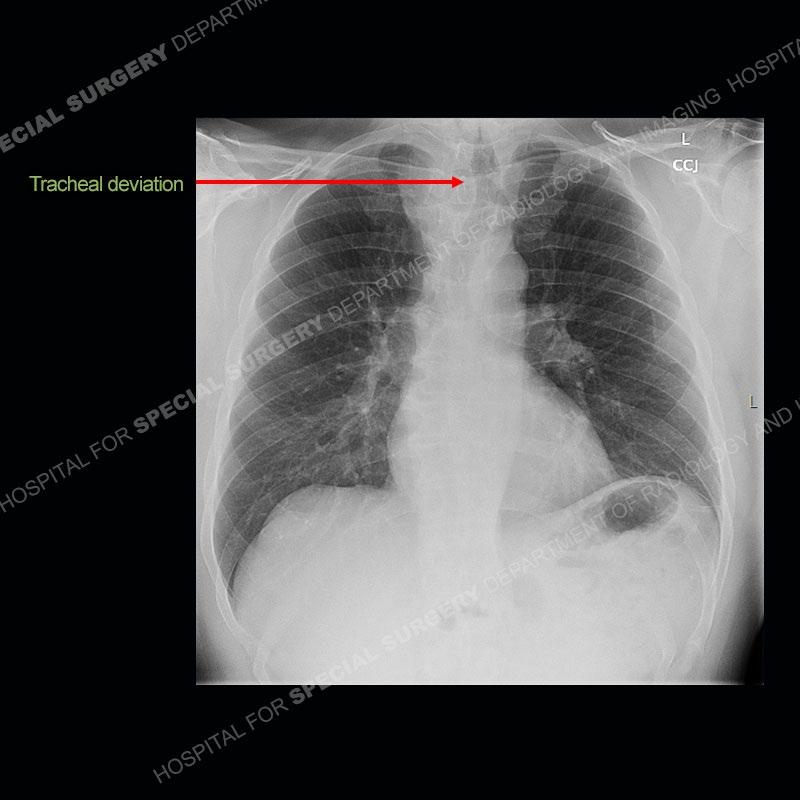

Findings

The chest radiographs demonstrate a leftward deviation of the trachea. CT images demonstrate a large, somewhat heterogeneous mass of the thyroid that extends outside the confines of the thyroid tissue. There is a subtle, enhancing soft tissue mass of the proximal right humerus. Slightly prominent mediastinal lymph nodes are present with additionally, multiple supraclavicular lymph nodes.

Over the years we have shown a couple of these cases which may be considered more so an “eye test” then anything else. In clinical practice, these are often very difficult cases as the initial finding of the tracheal deviation may be easily overlooked. Screening radiographs are clearly most often used to assess cardiopulmonary function before induction of anesthesia but at times other findings of great and unfortunately grave consequence can be found. The evaluation of the incidental thyroid mass on CT and MRI is an ever changing situation. Parameters such as age of patient, extension outside of the thyroid, enhancing nodules, and local invasion of lymph nodes are evaluated to see if a lesion needs to be further evaluated.